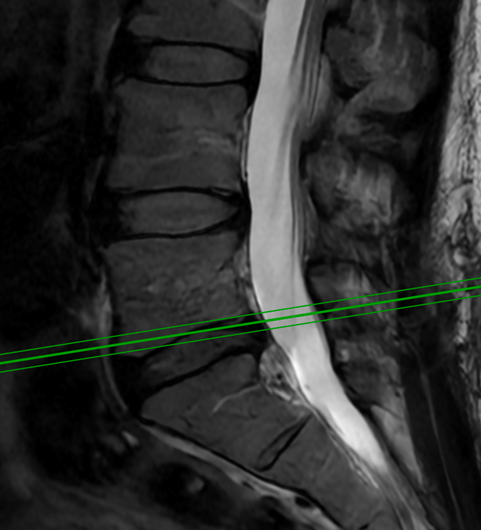

This 62-year-old female presents with chronic intractable low back pain with radiation down the front of her thighs. The patient had had two prior fusion surgeries: […]